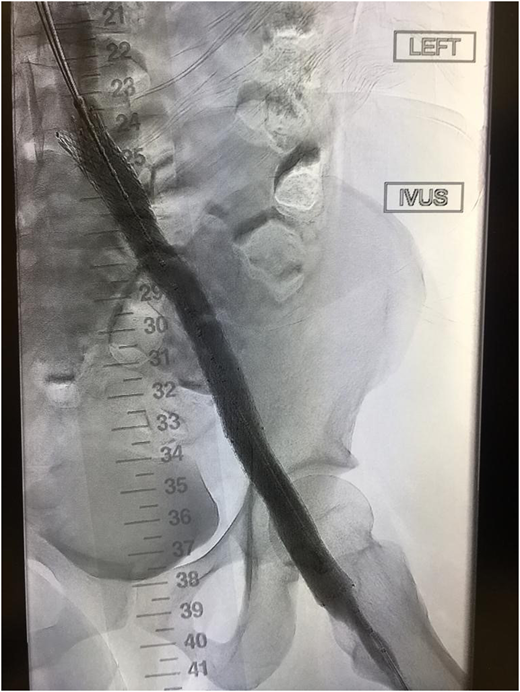

Severe PTS is often due to a chronic outflow obstruction, mainly the iliac vein, since there is usually poor collateralization of this vessel. Studies suggest when patients have severe symptoms; venous stenting is indicated when the obstruction is >50%, superficial collaterals form (Figures 2 and 3), and there is reflux in the deep and/or superficial veins.10 Femoropopliteal DVTs are best treated with anticoagulation only.

Improved vascular flow after venous stenting using the Abre stent (Medtronic).